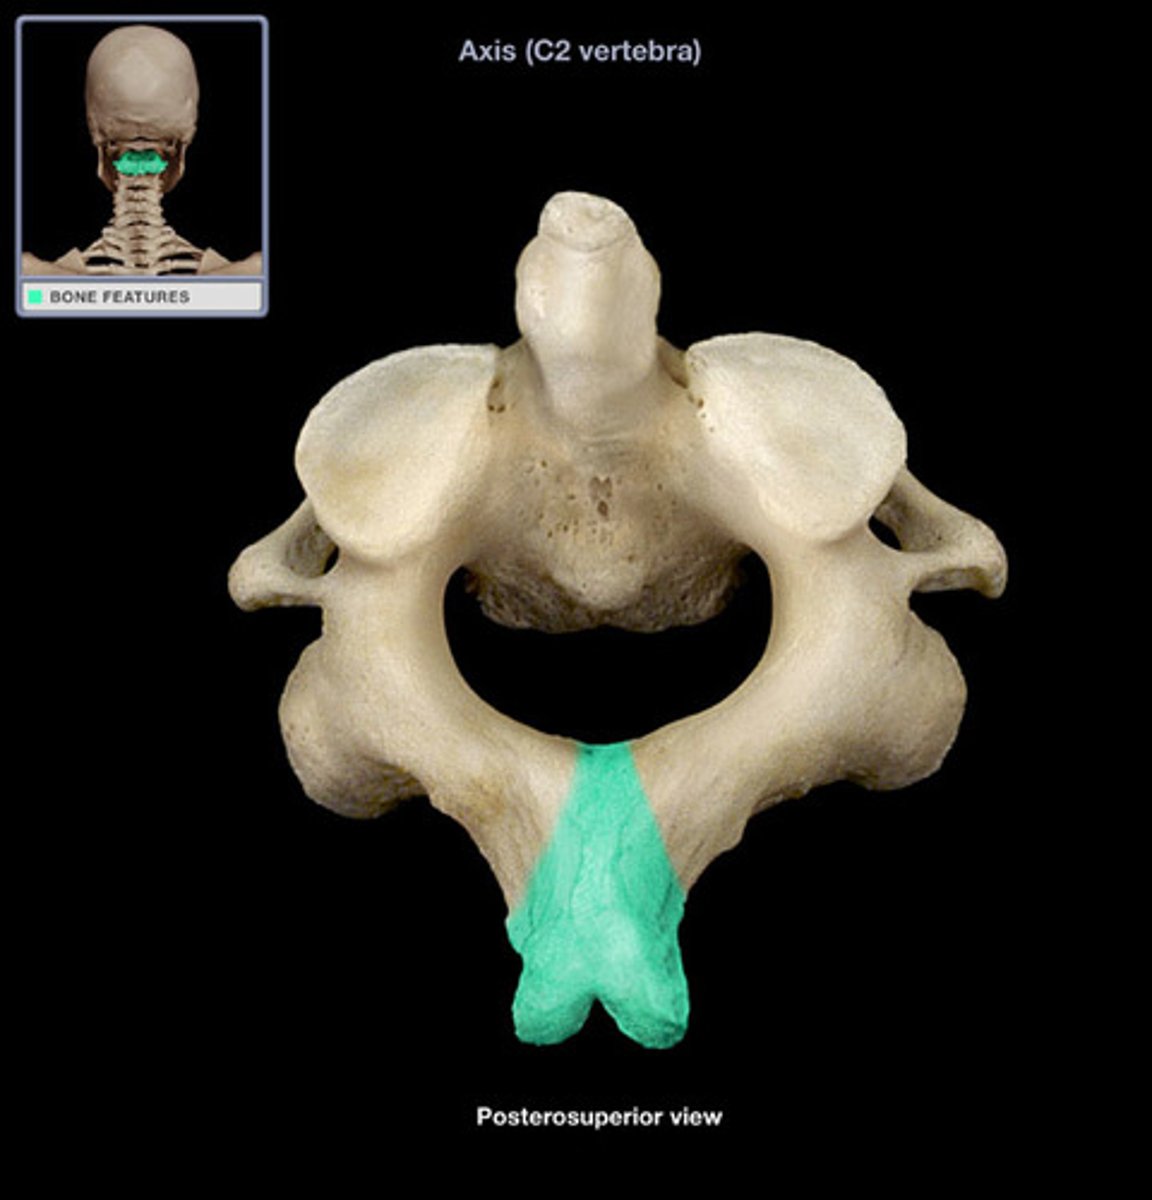

Axis

"no motion"

Spinous Process of axis